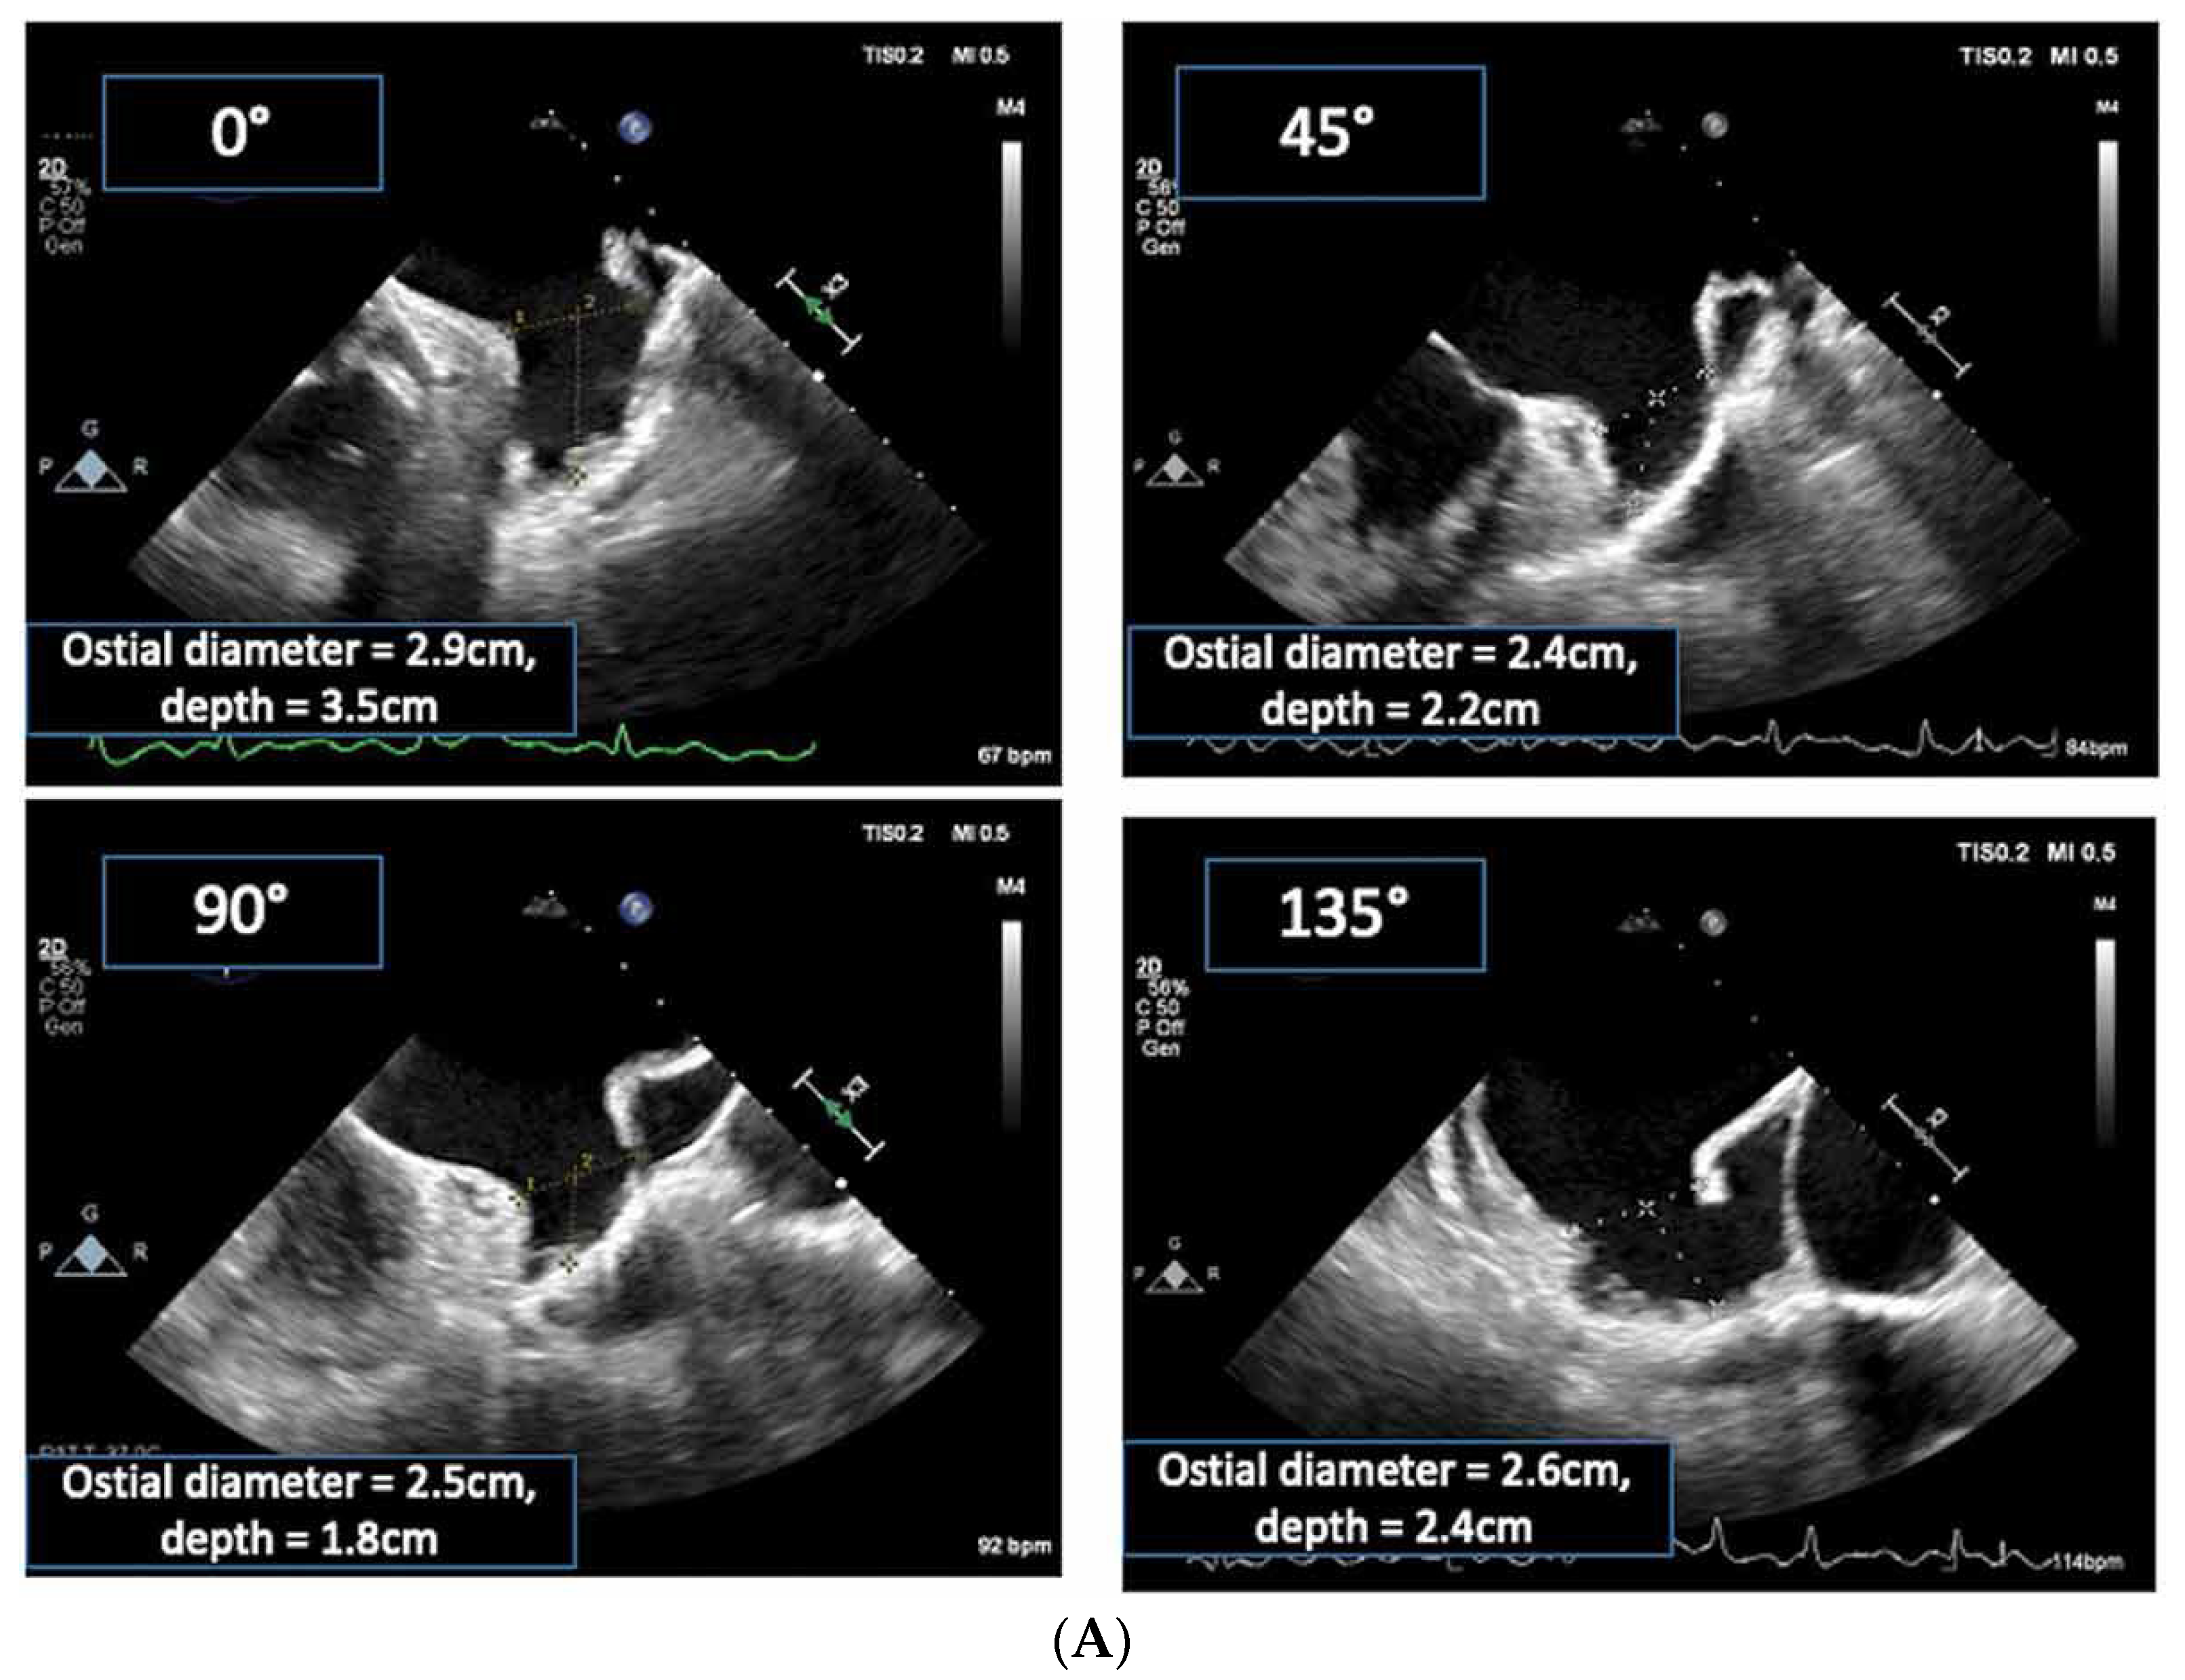

2.2.2. LAA Measurements (Anatomy and Morphology)